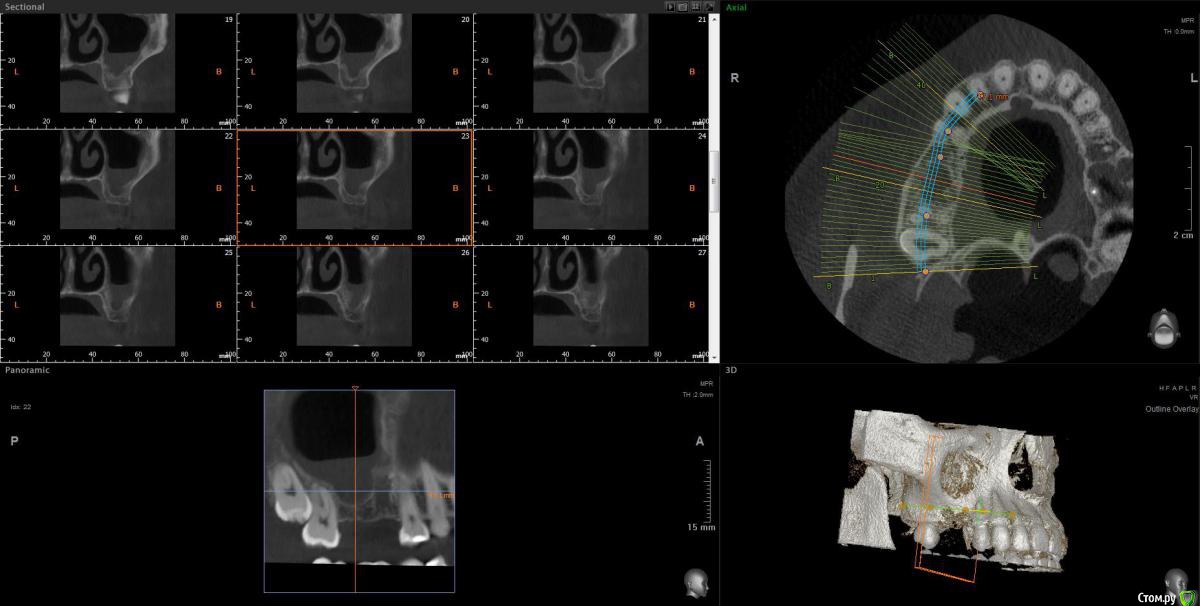

wladdX Опубликовано 30 июня, 2020 Поделиться Опубликовано 30 июня, 2020 Несколько скриншотов из КЛКТ 2 Ссылка на комментарий

колесников Опубликовано 30 июня, 2020 Поделиться Опубликовано 30 июня, 2020 Есть жидкость в пазухе на момент снимка. Можно только предполагать что является причиной воспаления,полной картины нет. Возможно это рельеф дна пазухи. В области 6ки углубление,где как в колодце застаивается слизь и прочее что попадает в полость и естественного дренажа не происходит. Я бы рекомендовал поставить 2 импланта 5,6. В области 6го провести закрытый синуслифтинг. Рельеф дна пазухи выровняется и вероятно обострений больше не будет. По крайней мере процессы происходящие в пазухе никак не повлияют на имплантацию,тогда как имплантация может купировать процессы в пазухе. Ссылка на комментарий

Оvzaika Опубликовано 1 июля, 2020 Автор Поделиться Опубликовано 1 июля, 2020 Несколько скриншотов из КЛКТ 25_1.jpg25_2.jpg26_1.jpg26_2.jpgH_M.jpgСпасибо! Ссылка на комментарий

Оvzaika Опубликовано 1 июля, 2020 Автор Поделиться Опубликовано 1 июля, 2020 Есть жидкость в пазухе на момент снимка. Можно только предполагать что является причиной воспаления,полной картины нет. Возможно это рельеф дна пазухи. В области 6ки углубление,где как в колодце застаивается слизь и прочее что попадает в полость и естественного дренажа не происходит. Я бы рекомендовал поставить 2 импланта 5,6. В области 6го провести закрытый синуслифтинг. Рельеф дна пазухи выровняется и вероятно обострений больше не будет. По крайней мере процессы происходящие в пазухе никак не повлияют на имплантацию,тогда как имплантация может купировать процессы в пазухе.добрый день! пока есть воспаление за имплантацию 6-ки никто не берется, вчера один врач предложил сделать синусотомию под местным наркозом убрать все что будет в пазухе подождать месяц заживления и потом делать синус-лифтинг. Ссылка на комментарий

колесников Опубликовано 1 июля, 2020 Поделиться Опубликовано 1 июля, 2020 добрый день! пока есть воспаление за имплантацию 6-ки никто не берется, вчера один врач предложил сделать синусотомию под местным наркозом убрать все что будет в пазухе подождать месяц заживления и потом делать синус-лифтинг. как ни абсурдно звучит,я бы предложил вначале провести имплантацию с синуслифтингом,а после понаблюдать и возможно санировать пазуху. Если сделать как Вам предлагали,есть вероятность что пауза будет не месяц а больше,а за это время в эту ямку снова соберётся жидкость с последующим инфицированием. Нет ямки-нет условий для застоя жидкости. Ссылка на комментарий